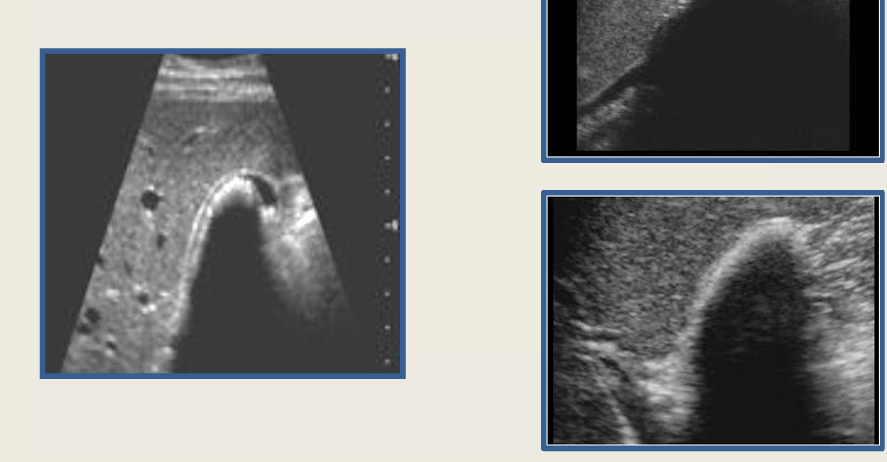

5

New cards

term image

gb polyps

6

adenomyomatosis

7

strawberry GB

8

mucocele